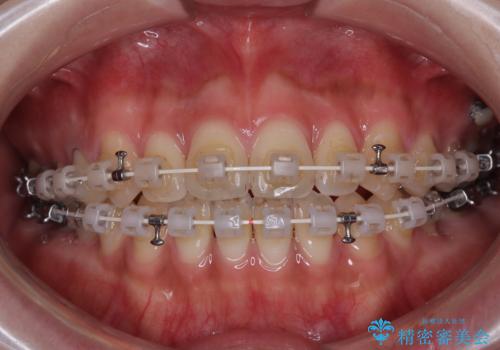

開咬をワイヤー装置で矯正治療

- 矯正装置

- 審美装置

- 上下前歯が非接触となっている咬み合わせを気にして来院された患者様です。

開咬となっている原因の大半は、舌の突出癖によるものであるため、治療開始前から舌のトレーニングを開始し、スムーズに治療が進むようにしました。

開咬の方は、インビザライン矯正治療が適していますが、自己管理の煩わしさと、転勤の可能性がありマウスピース矯正であると通院しなくなるだろうとのことで、ワイヤー装置にて矯正治療を行うこととしました。